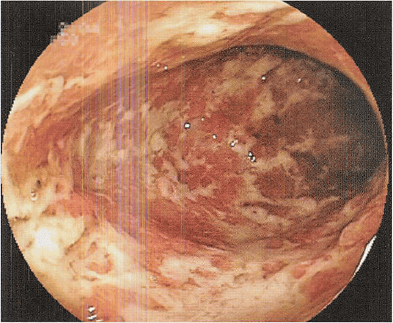

⭕️の位置が尺骨神経の通り道です

この部分が圧迫を受けると腱鞘炎になります

写真のように小指と薬指半分が痺れたり痛みがでます

これは尺骨神経が支配している範囲です